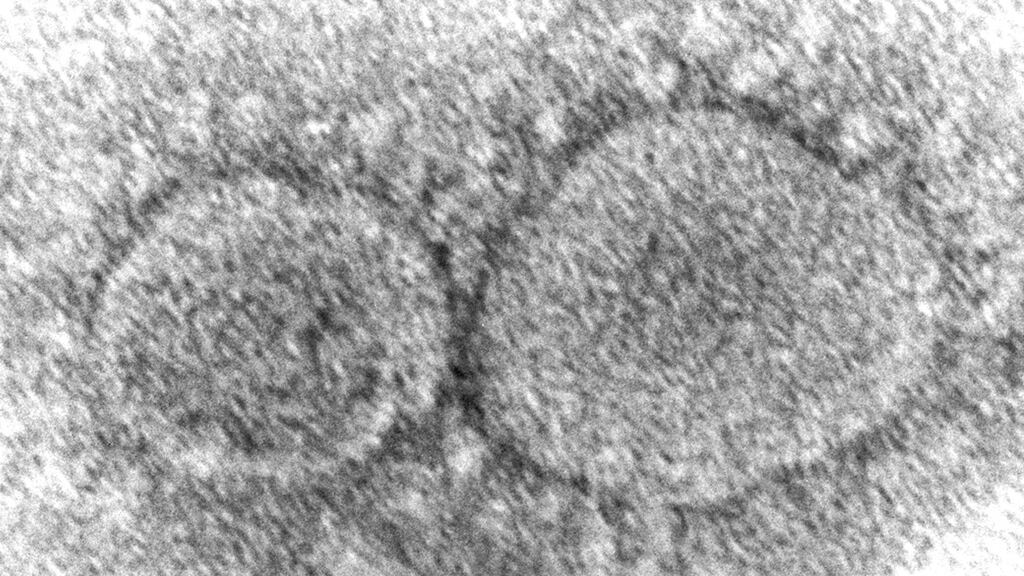

La Cámara de Representantes estadounidense votó por unanimidad el viernes para hacer pública la información de los servicios de inteligencia sobre los orígenes del COVID-19, en una muestra de apoyo bipartidista en vísperas del tercer aniversario del inicio de la mortífera pandemia.

La orden de hacer pública la información se concentró en la información de inteligencia relacionada con el Instituto de Virología de Wuhan, China, y los posibles vínculos entre la investigación realizada allí y el brote de COVID-19 que la Organización Mundial de la Salud declaró pandemia en marzo de 2020.

Las agencias de inteligencia estadounidenses no se ponen de acuerdo sobre si la fuente probable del virus es una filtración del laboratorio o de origen animal.